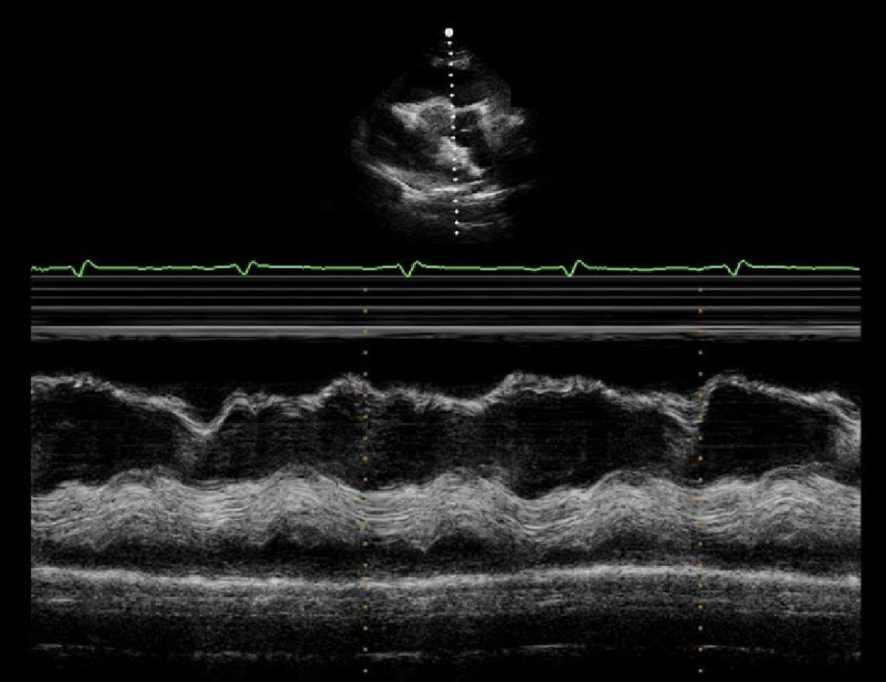

The image displays a focal wall structure and motion abnormality caused by?

Focal HCM

Which of the following valvular abnormalities is commonly associated with the abnormality on the image?

SAM